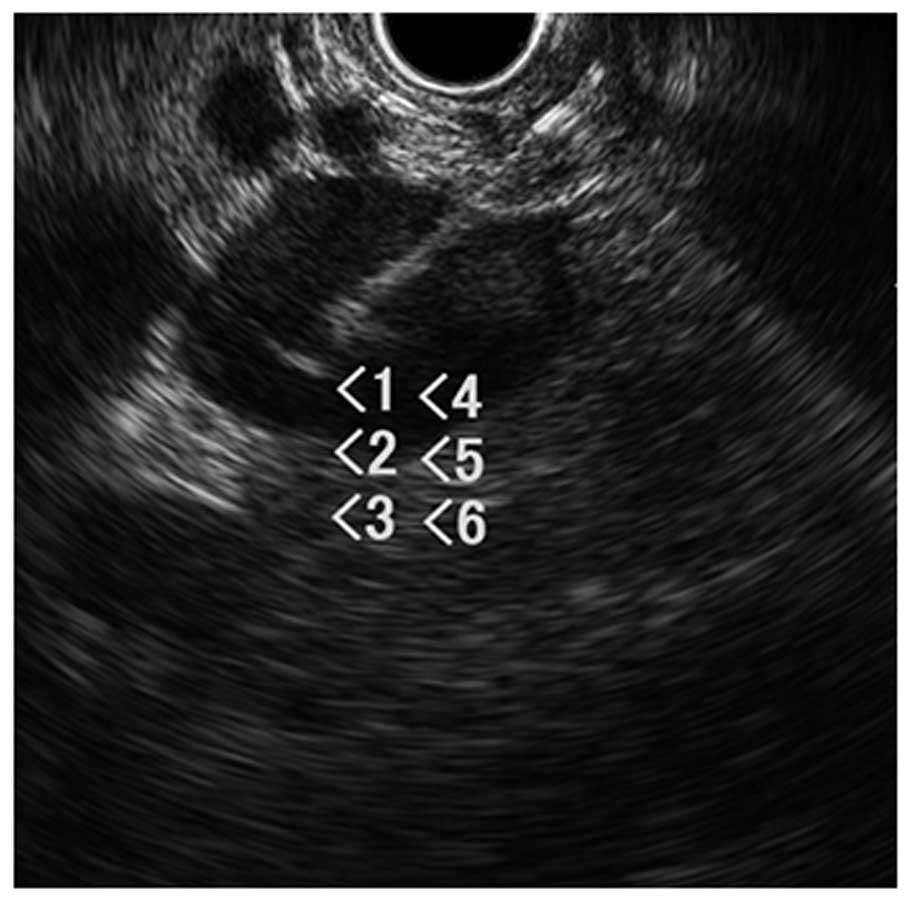

Figure 2.

Endoscopic ultrasonography revealed a homogeneous hypoechoic mass (26×20 mm2) in the left adrenal gland. Numbers refer to biopsy sample.

A 76-year-old female with a complaint of cognitive dysfunction visited the Department of Neurosurgery, Kanazawa University Hospital (Ishikawa, Japan). The patient was previously diagnosed with RCC of the right kidney in the Department of Urology, Public Central Hospital of Matto (Ishikawa, Japan) 19 years previously. The right kidney was removed and the patient received no adjuvant therapy at that time. A physical examination revealed no findings other than disorientation, and laboratory data, including tumor markers, revealed no notable findings. Brain gadolinium contrast-enhanced magnetic resonance imaging uncovered several nodules (Fig. 1), whereas chest and abdominal computed tomography (CT) identified a single nodule in the right lower lobe of the lungs, a mass in the left adrenal gland and an osteolytic lesion in the left pelvis (Data not shown). On the basis of these findings, the patient was diagnosed with a metastatic brain tumor. Following diagnosis, the patient received stereotactic radiosurgery with gamma knife therapy for the brain lesions. To identify the primary lesion, the present case study attempted to obtain histological confirmation of the adrenal lesion using EUS-FNA, available in the department. FNA was performed via the transgastric approach with linear EUS (GF-UCT260; Olympus, Tokyo, Japan), and two passes were made with a 19-gauge needle (Sono Tip Pro Control; Medi-Globe, Rosenheim, Germany). EUS revealed a homogeneous hypoechoic mass with a maximum diameter of 26 mm within the left adrenal gland (Fig. 2). Tissue obtained from the aspirated material revealed clear cytoplasmic and vascular stroma (Fig. 3A), and these findings were similar to those of the nephrectomy specimen obtained 19 years previously (Fig. 3B). Histologically, a definitive diagnosis of metastatic RCC was made. Based on the diagnosis, the patient received targeted therapy with pazopanib (Votrient®; GlaxoSmithKline, Middlesex, UK; 800 mg orally, once/day). The majority of the metastatic lesions of RCC regressed following 1 month of treatment (Fig. 4A–C).